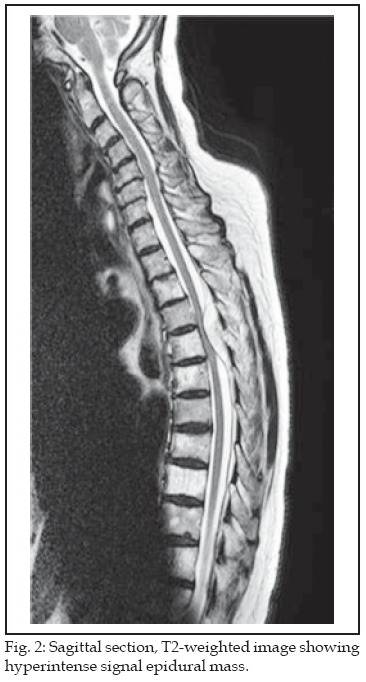

Neurological examination on current presentation revealed decreased sensation of pain, position and touch below T6, power in lower limbs was Grade 4, reflexes were normal and Babinski’s reflexes were negative. X-rays did not show any abnormality. Routine blood investigations including Myeloma screen were normal. In view of her symptoms a suspicion of thoracic spinal cord lesion was raised and thoraco-lumber MRI scan was requested. MRI scan showed a mass compressing onto the cord extending from the posterior element of T4 and T5 (Fig 1 & 2). There was mixed signal characteristics in this vertebral body and adjacent bony structures with low signal on T1 (Fig-1), high on T2 (Fig-2) and evidence of some enhancement following Gadolinium on T1 sequences. Next day she developed urinary retention and her Babinski’s reflexs were positive.

MRI more accurately characterizes and demonstrates the location and extent of compression on the spinal canal. From our review of literature and MRI finding in present case, these lesions are isointense with spinal cord on T1-weighted images and hyper intense on T2-weighted images and showed homogenous strong enhancement in all patients.3,5,7,20-23